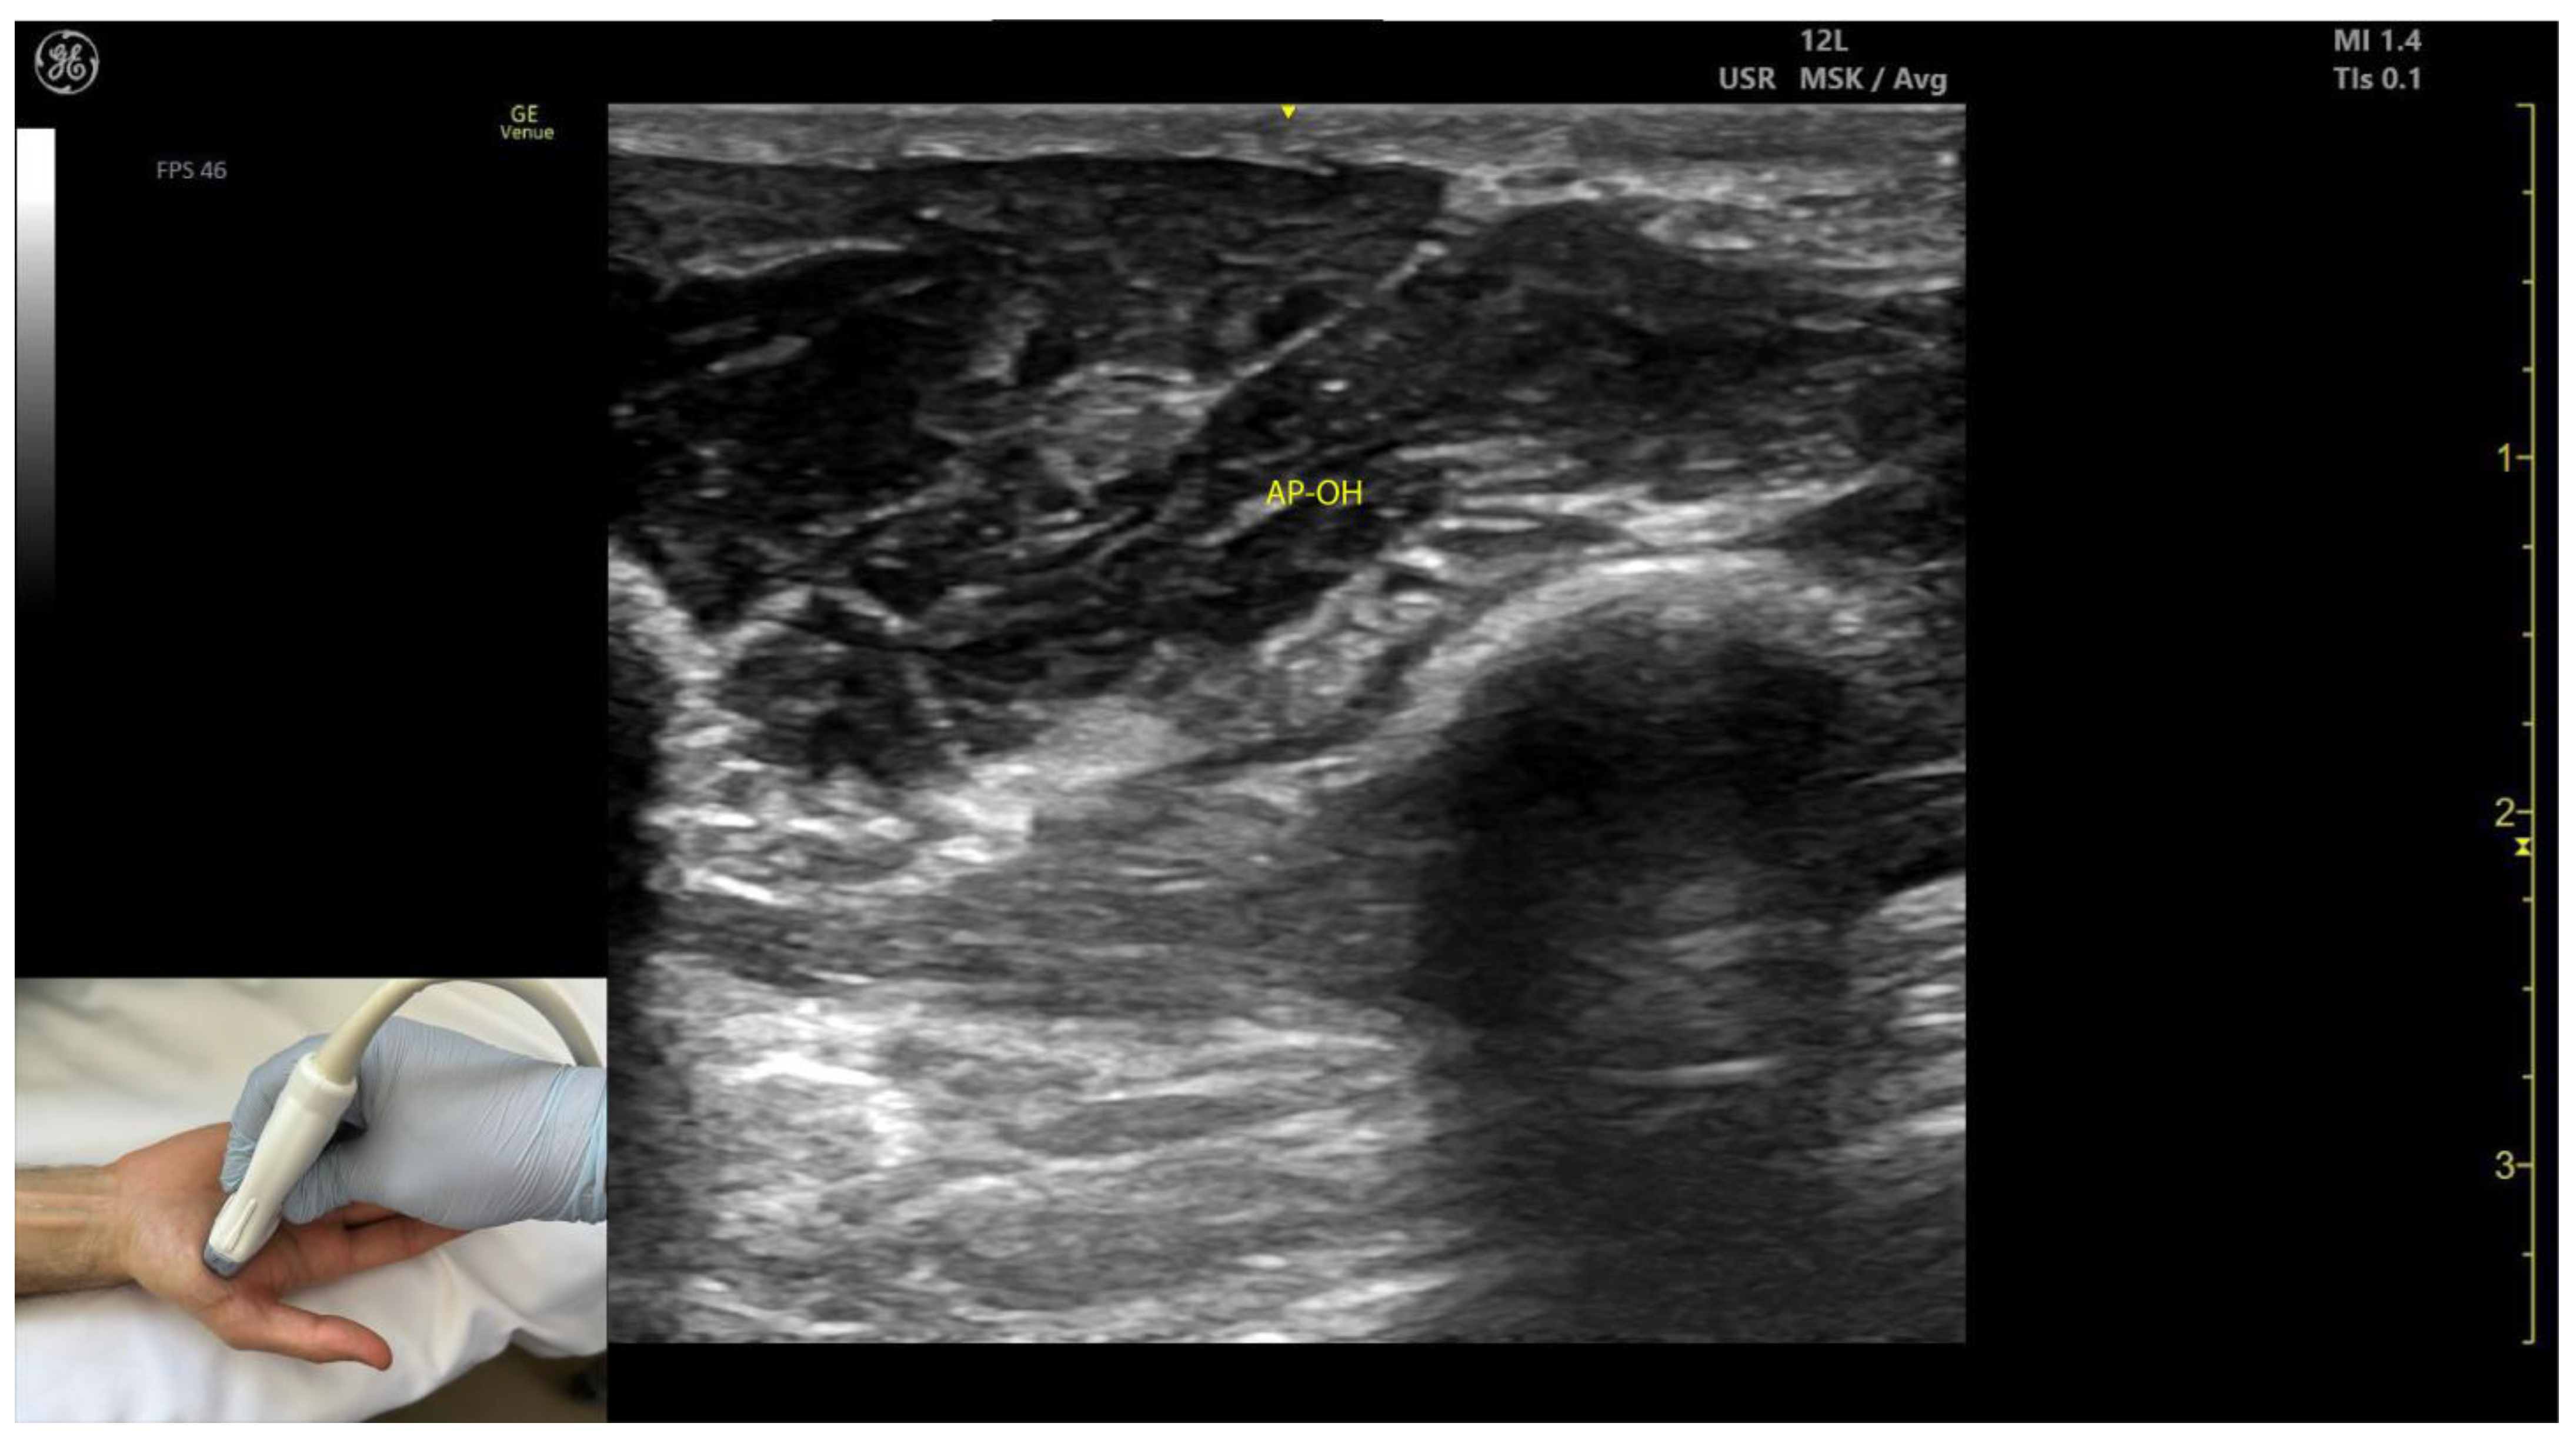

2.11.3. Key Ultrasound Landmarks (Figure 10 and Figure 11)

- Two heads: The AP consists of a transverse head and an oblique head: (i) The transverse head is identified with the transducer placed transversely on the palmar aspect at the midpoint of the second and third metacarpals. Scanning proximally (approximately 1 cm) reveals the muscle’s maximal thickness; (ii) the oblique head is visualized by angling the transducer approximately 45 degrees laterally toward the thumb. This head is located lateral to the FPL tendon and the FPB, with the first dorsal interosseous muscle in its depth [59,60];

- External fascia: The AP muscle is characterized by a pronounced fascia that clearly separates it from adjacent muscle masses, facilitating precise localization during BoNT-A injections.

- Dynamic evaluation: Contraction of the AP is observed during thumb adduction at the CMC and MCP joints or during pinch movements, such as bringing the thumb tip into contact with the index finger tip.

- In our clinical practice, BoNT-A is administered into the point of maximum muscle thickness, as determined by ultrasound. The injection is typically performed approximately 1 cm proximal to the midpoint of the second and third metacarpals, with the transducer angled 45 degrees toward the thumb to target both the transverse and oblique heads.